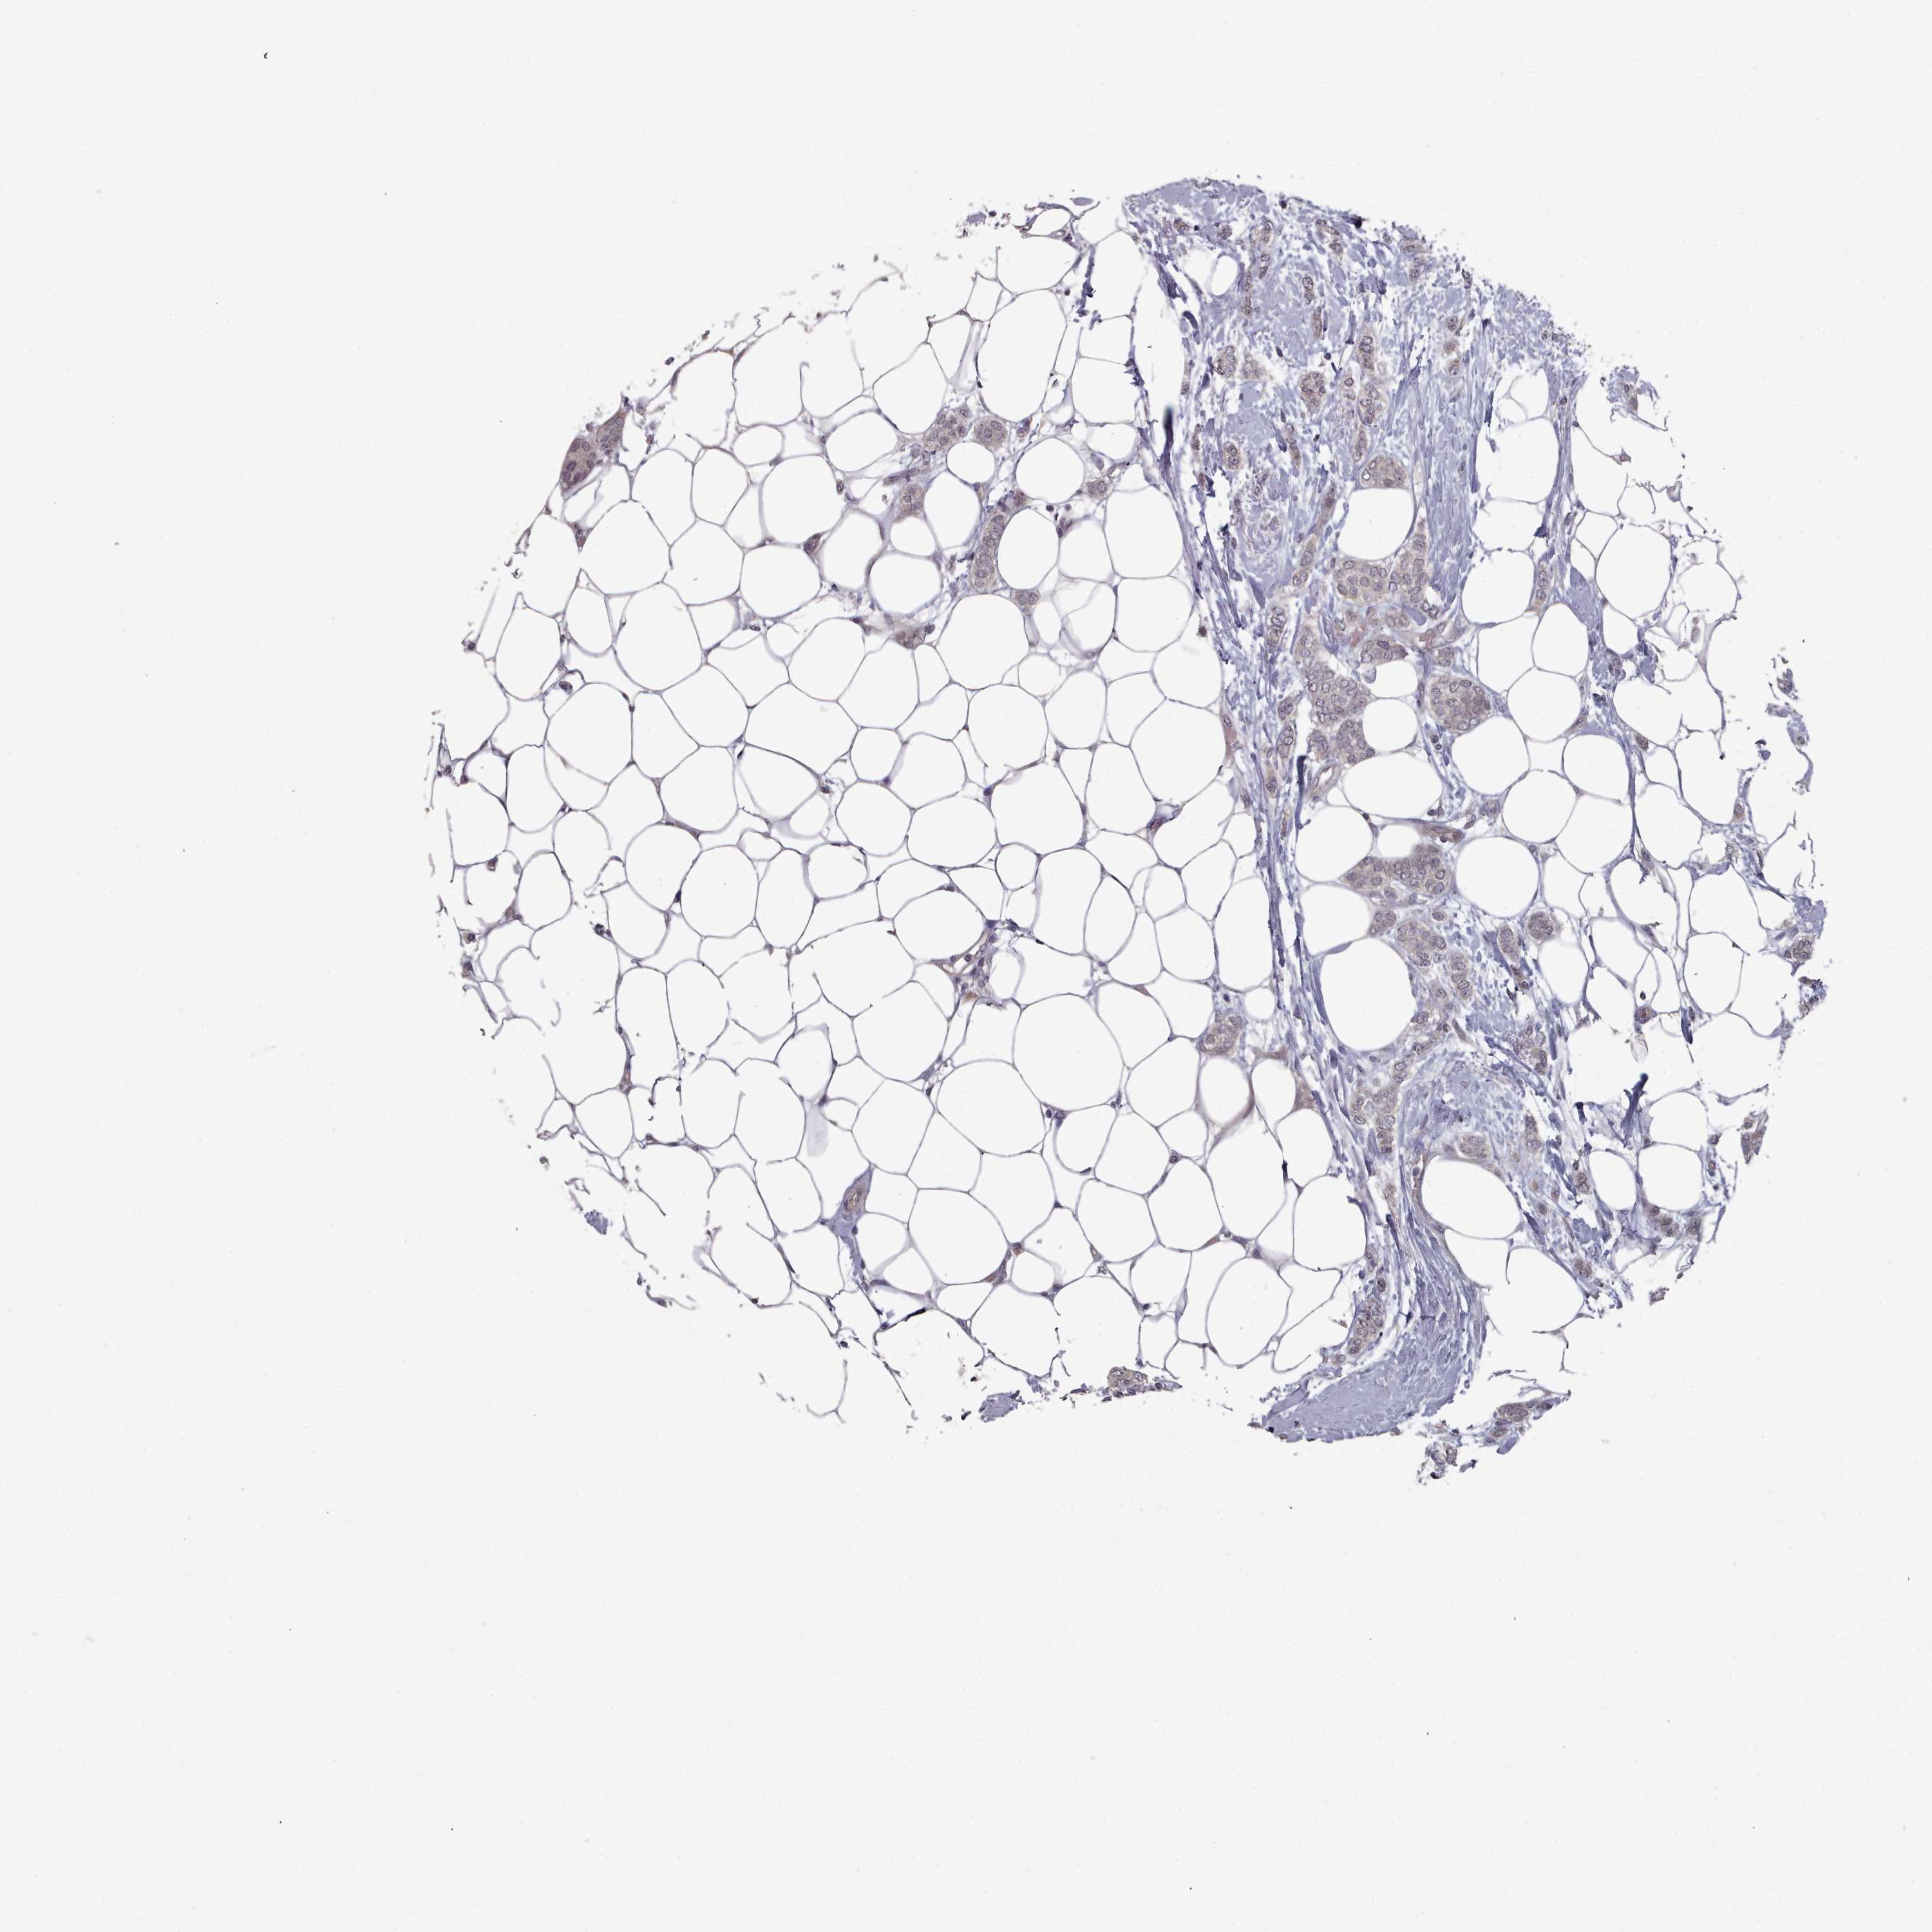

BRCA TCGA BRCA VALIDATION PROTEIN EXPRESSION